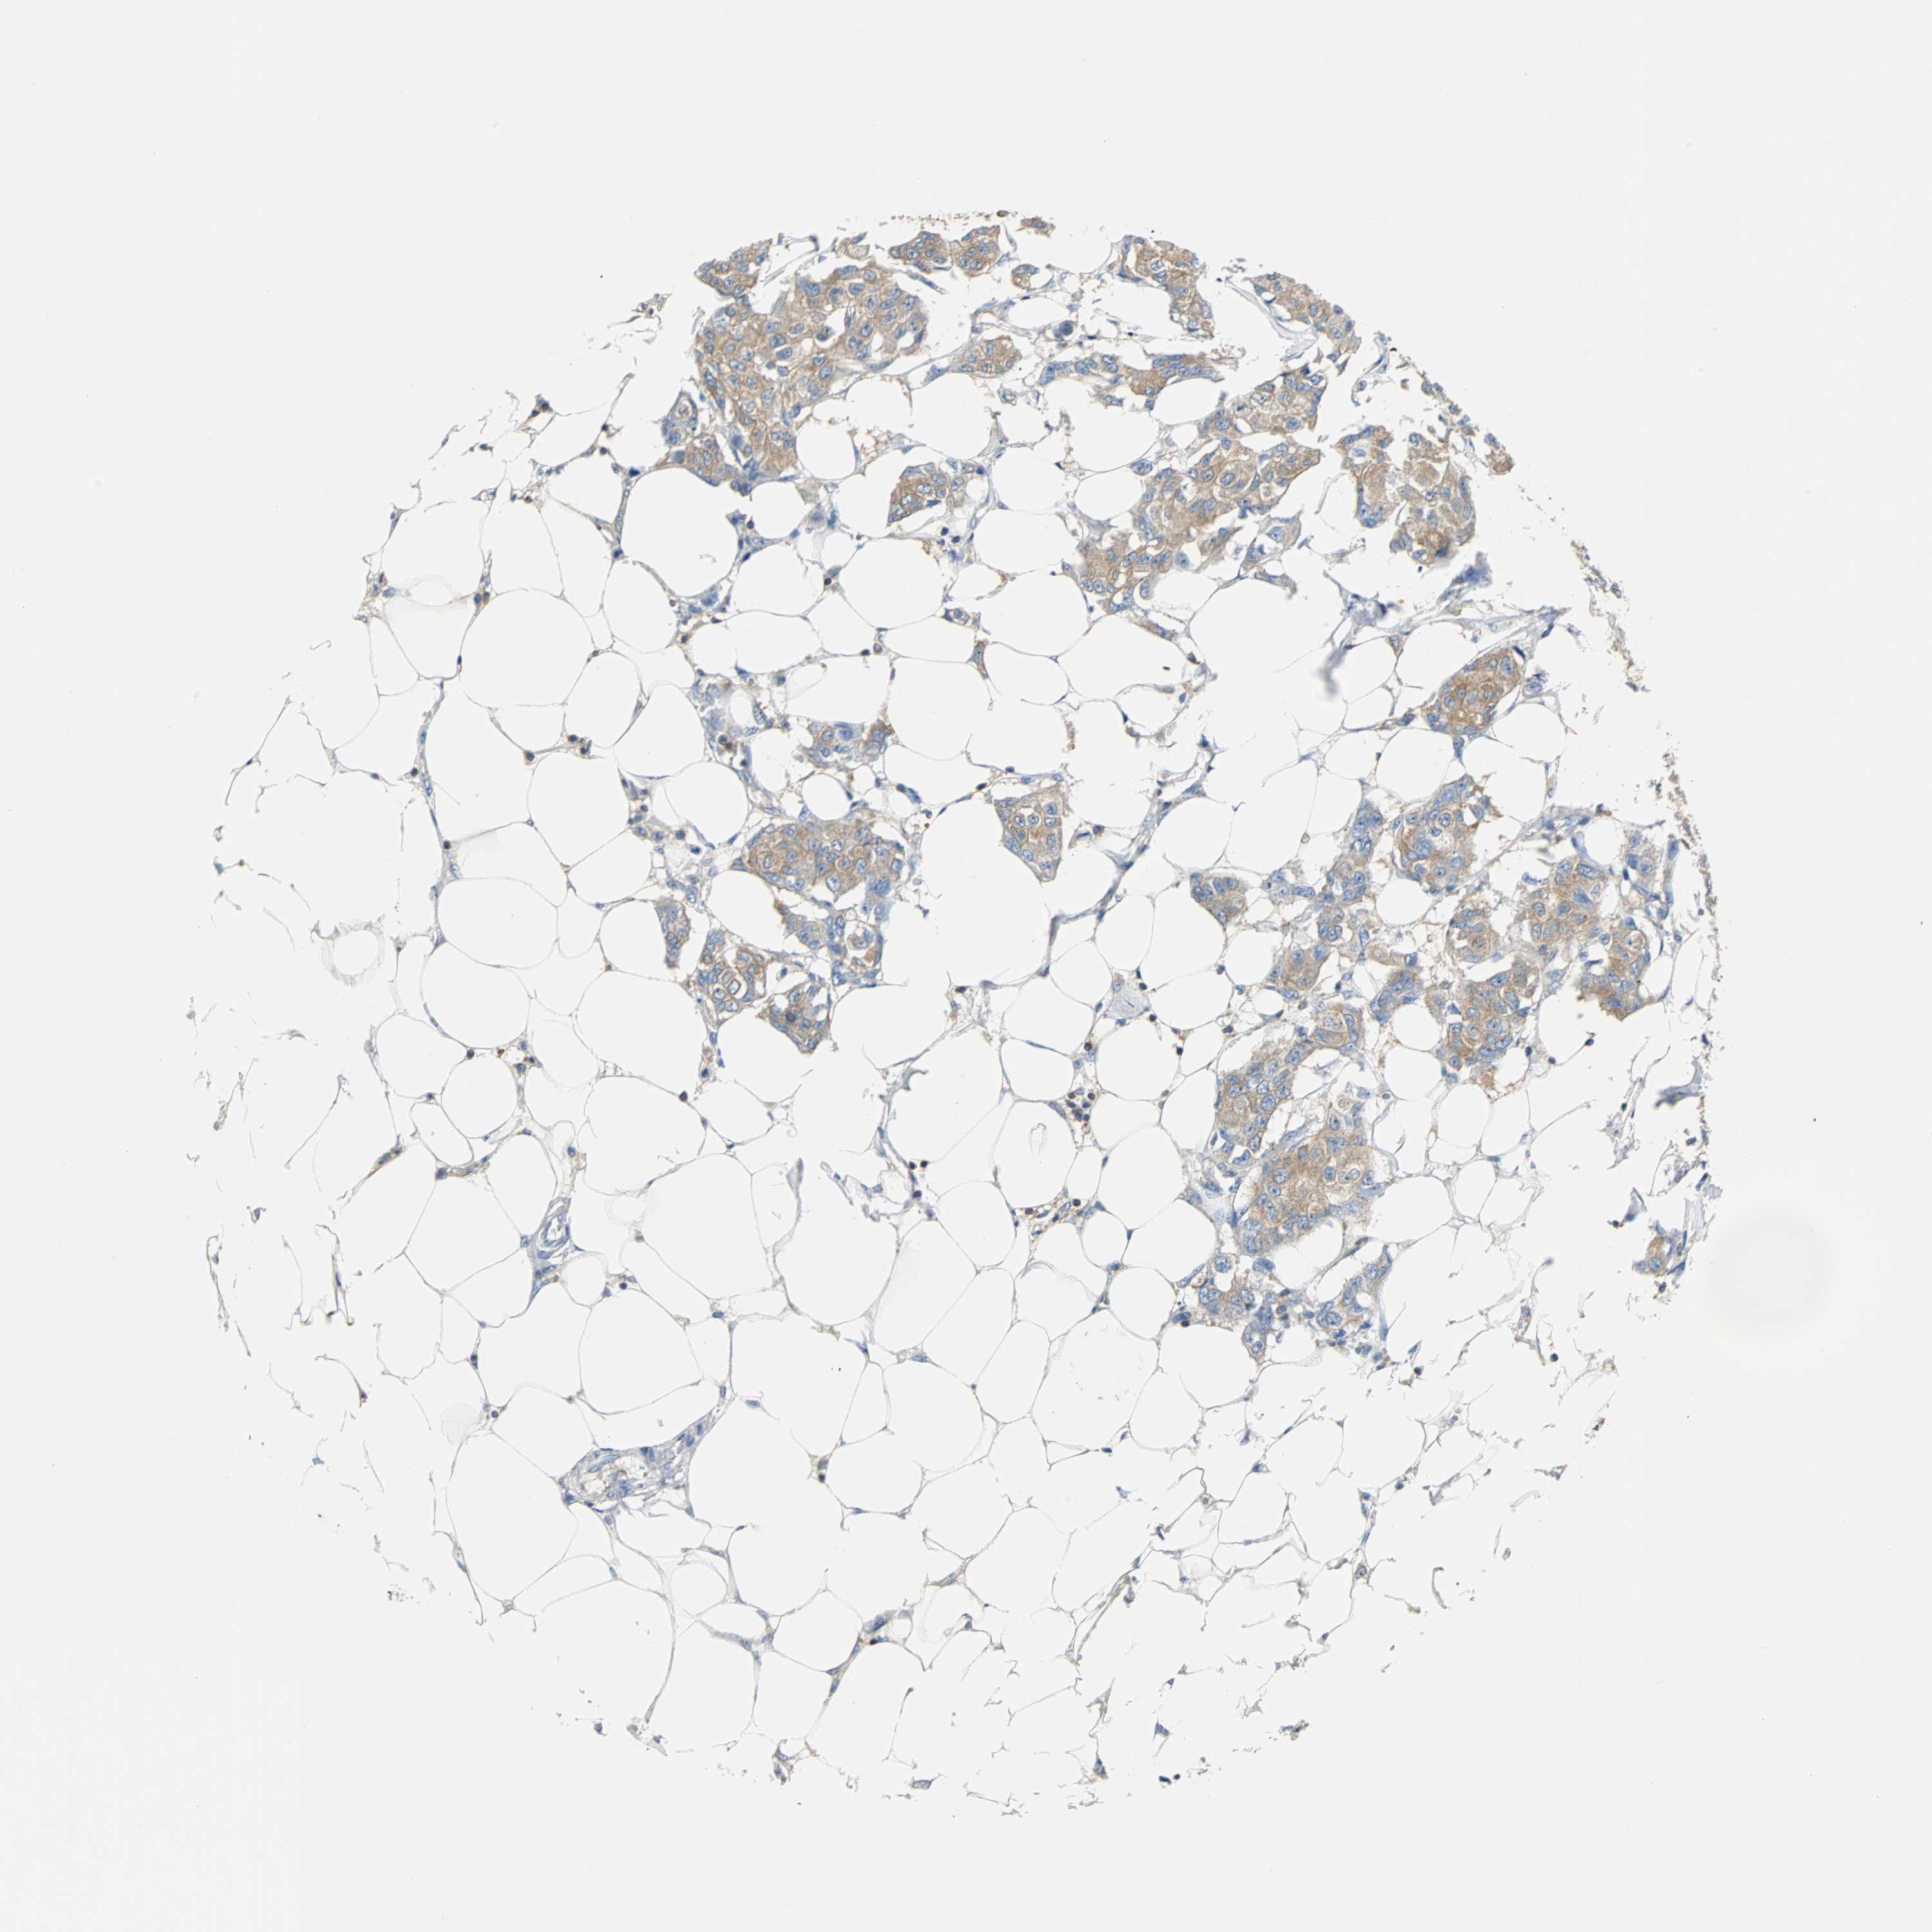

BRCA TCGA BRCA VALIDATION PROTEIN EXPRESSION